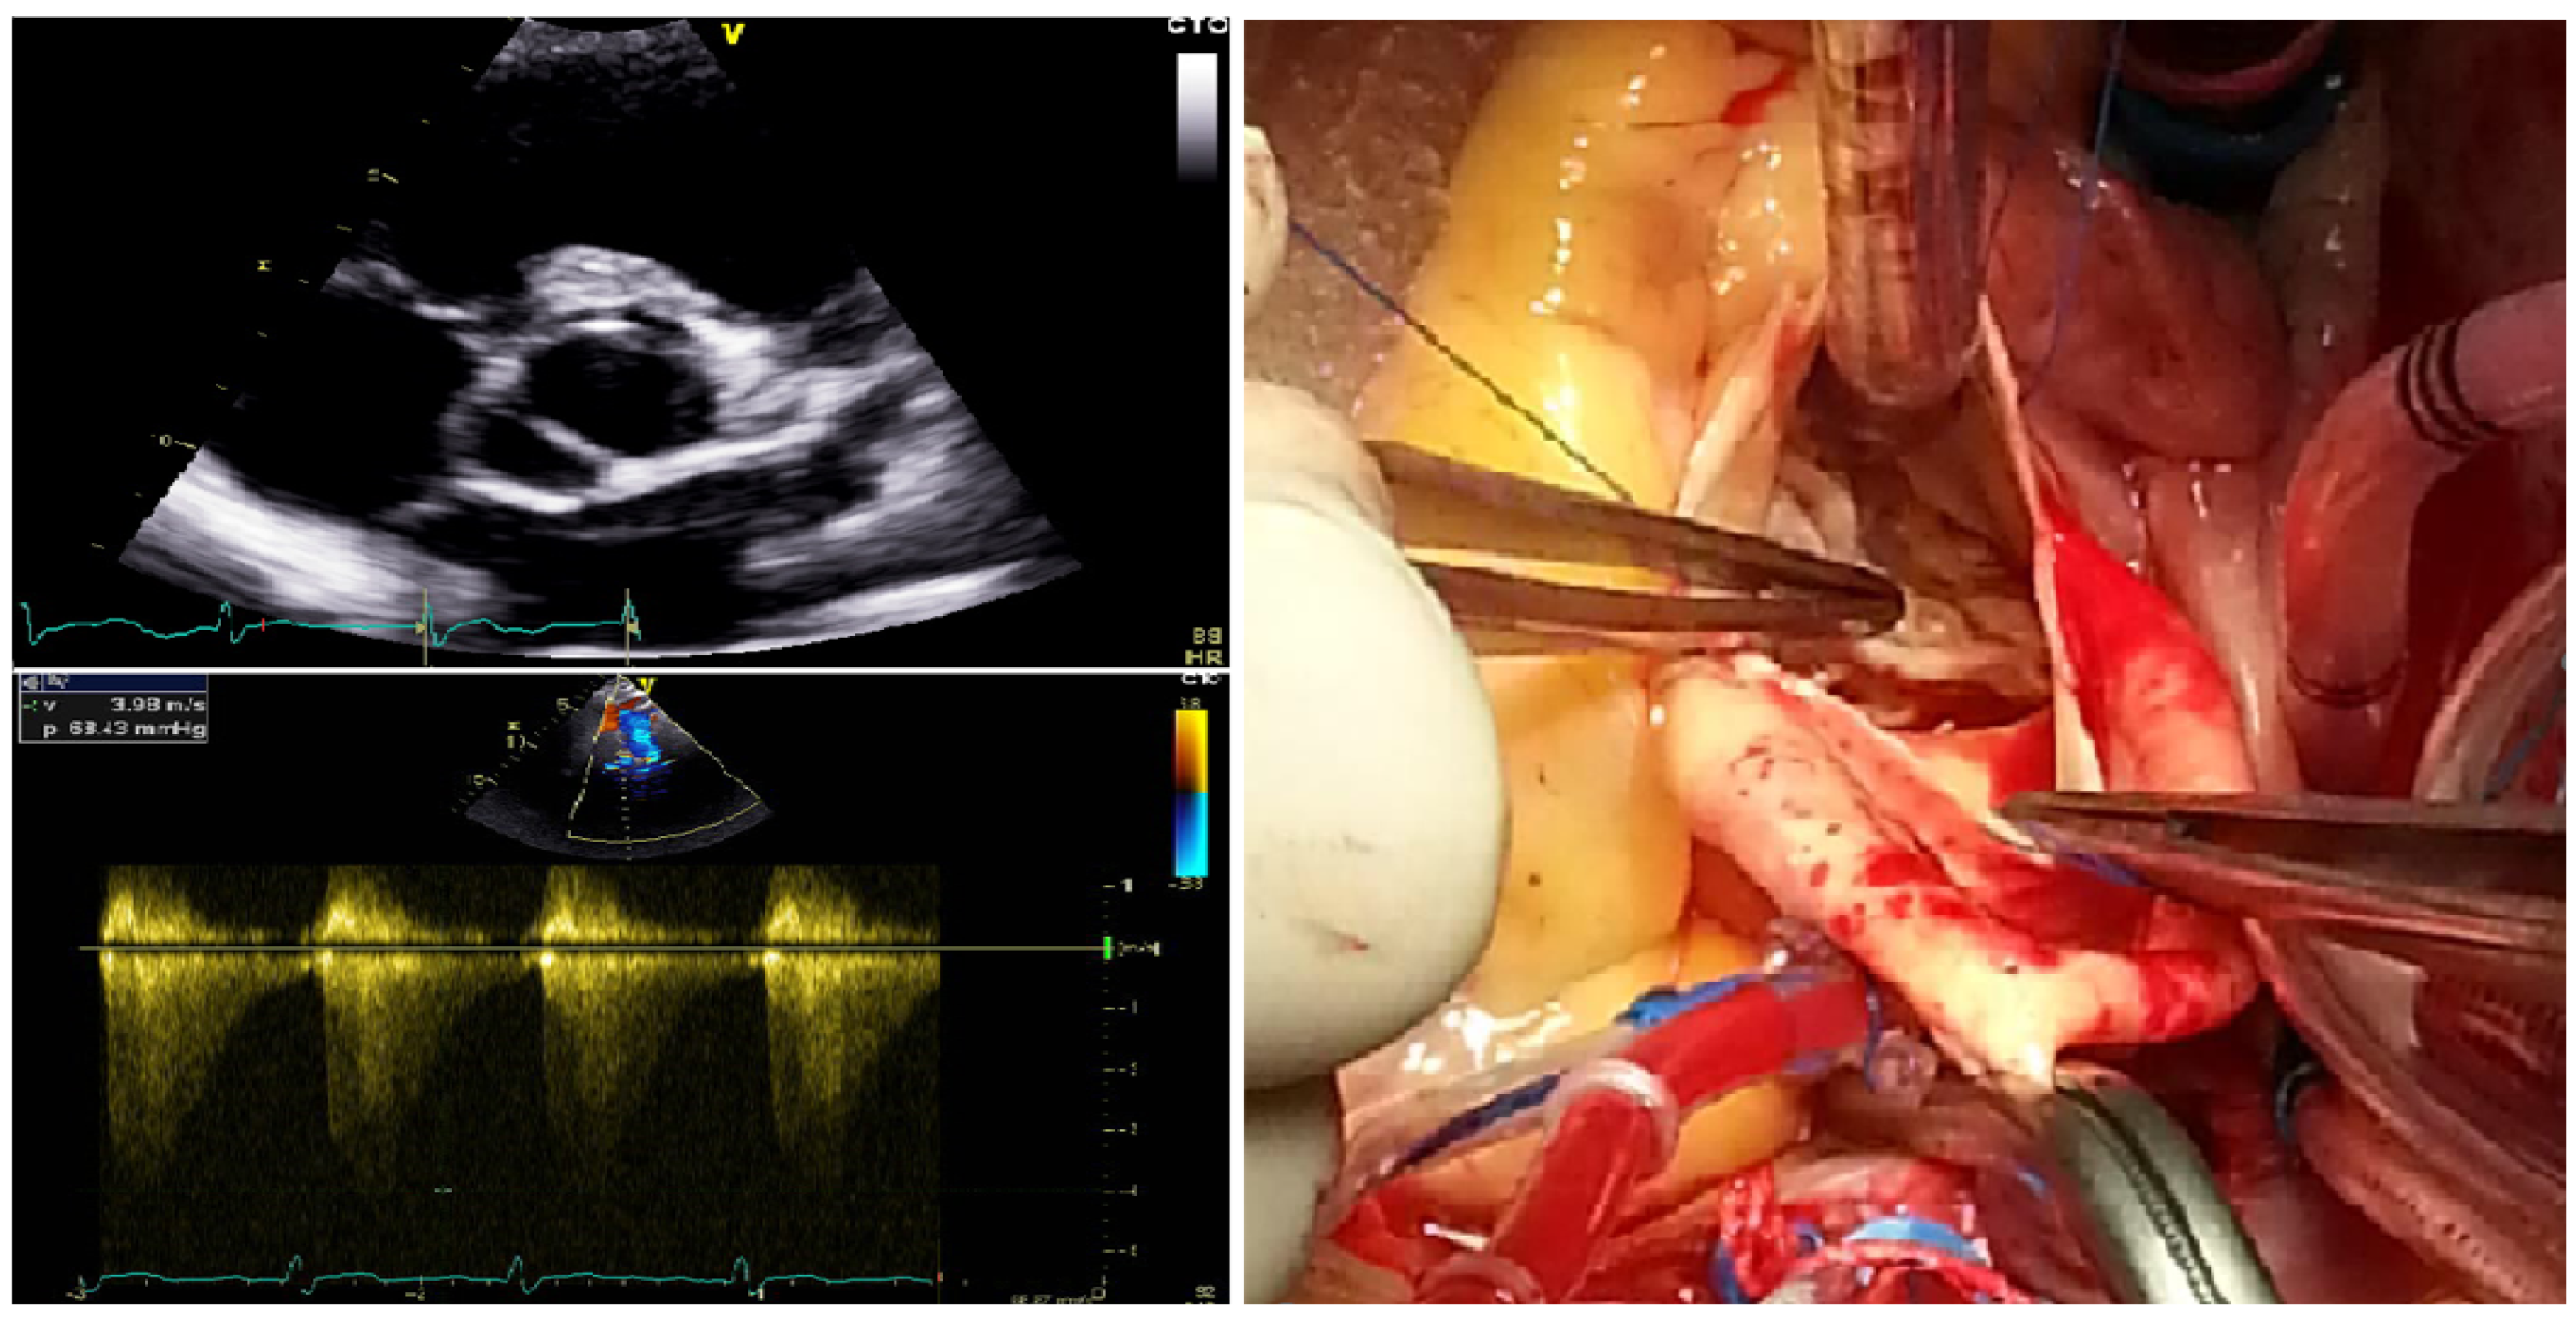

3.1. Clinical Characteristics of the Study Pedigree with BAV

3.2. A Novel Human BAV-Linked Locus on Chromosome 7p14